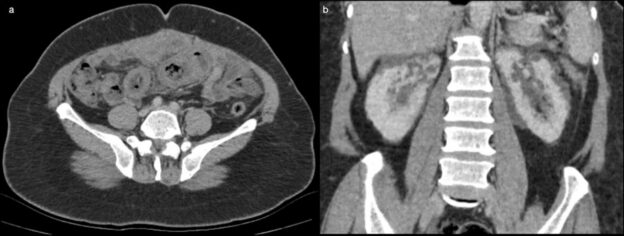

51-year-old woman with abdominal pain

A 51-year-old woman with no known chronic disease presented to the emergency department with abdominal pain for 15 days.